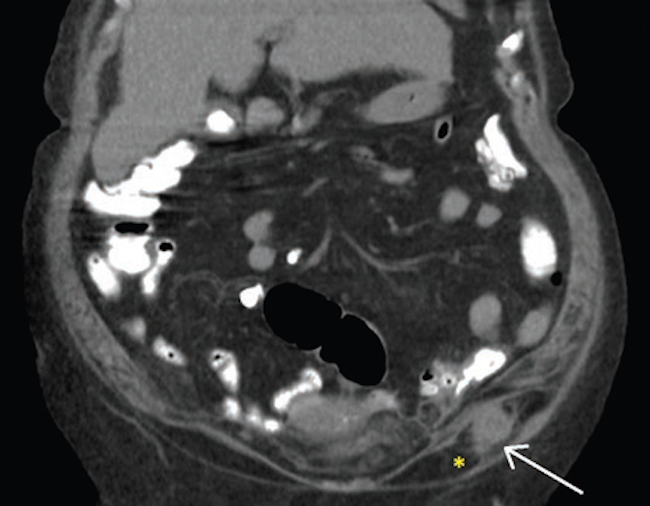

Dados los hallazgos ecográficos, se realizó una tomografía computada abdominal y pélvica, en la que se observaron una solución de continuidad de 22 mm en el flanco izquierdo (Fig. 1) y una imagen ovalada ligeramente edematizada (Fig. 2). En la cavidad pelviana se observó una imagen líquida de aspecto quístico de 91 × 87 × 81 mm, dependiente de anexo derecho (Fig. 3). Durante su internación, la paciente persistió con dolor a nivel referido y fue llevada a laparotomía exploratoria, en la que se halló un tumor abscedado sobre la aponeurosis del músculo oblicuo izquierdo, del que se tomaron muestras para anatomía patológica, y se drenó y corrigió la solución de continuidad en el acto quirúrgico. Se amplió el estudio microscópico con marcadores tumorales CA 125 y CA 19-9, que fueron positivos para metástasis de carcinoma primario de ovario (Fig. 4). Actualmente, la paciente está en manejo oncológico.